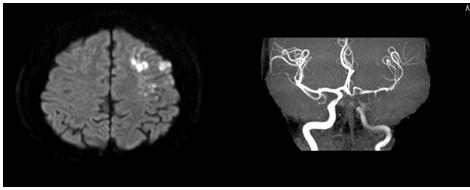

图11 左侧基底节区急性脑梗死,左侧MCA无明显狭窄,考虑为穿支动脉病变(图源 作者提供)